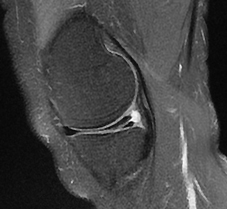

Meniscal Tears

Torn Medial Meniscus. CKC MRI

Horizontal tear of the posterior horn of the medial meniscus with a cyst

Complex horizontal lateral meniscal tear